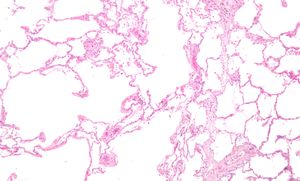

الپاثولوجيا العيانية للرئة تظهر انتفاخ الرئة المركزي بسبب التدخين. | |

يندرج تحت هذا المرض حالتان هما: الالتهاب الشعبي المزمن (chronic bronchitis) وهو وجود كحة وبلغم لمدة ثلاثة أشهر في سنتين متتاليتين والنفاخ الرئوي emphysema وهو تشخيصٌ تشريحيّ يصف تغيّر بُنية الرئتين من توسع الشعيبات الهوائية وتلف جُدر الحويصلات الهوائية.